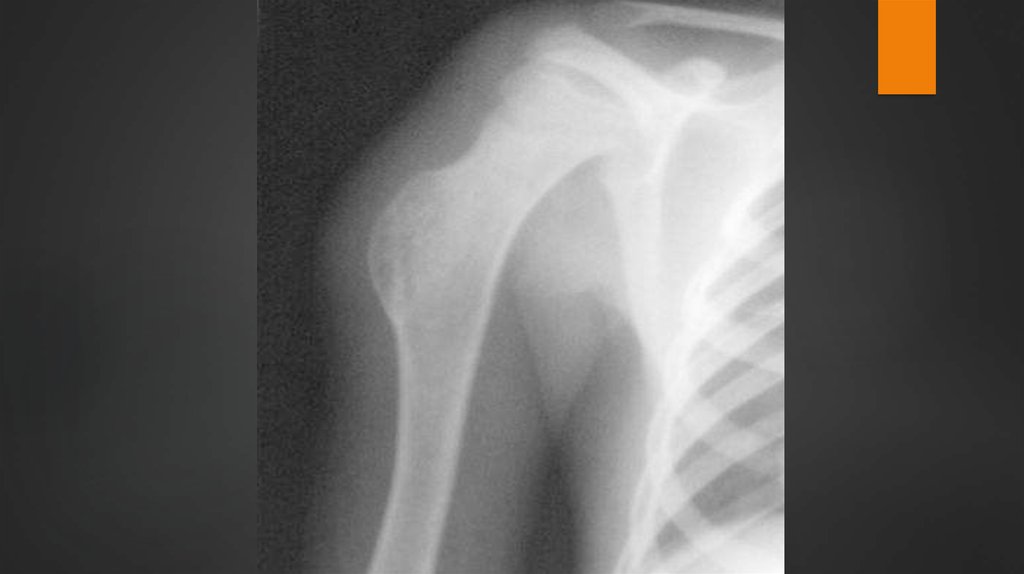

4. Рентгенологические признаки остеогенной саркомы:

— локализация в метафизе и прилежащей части

диафиза трубчатых костей;

— реакция надкостницы (периостит) в виде козырька

и спикул; — выявление опухоли в мягких тканях в виде

полусферической или веретенообразной тени на

уровне костных изменений;